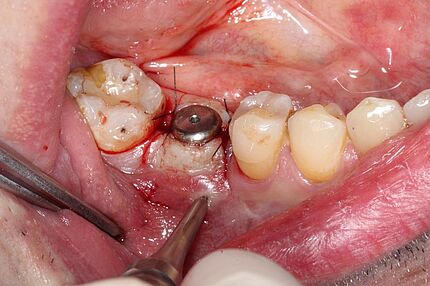

In den letzten Jahren ist eine Zunahme des Interesses an Knochenaugmentationen mit nicht erhaltungs- würdigen Zähnen erkennbar. Das Verwerfen von extrahierten Zähnen ist zurzeit noch tägliche Routine in Zahnarztpraxen und Kliniken. Dieser Fallbericht illustriert die Situation eines 62-jährigen Patienten, bei dem nach Entfernung der Oberkieferfrontzähne der Alveolarfortsatz einen komplexen knöchernen Defekt aufwies. Die Schaltlücke wurde zweizeitig rekonstruiert. Hierbei wurde der knöcherne Defekt mittels der Tooth Shell Technique nach Korsch unter Verwendung von autologem Dentin rekonstruiert und mit zwei Implantaten sowie Implantatkronen prothetisch versorgt. Abschließend erfolgte eine Transplantation von freier keratini-sierter Schleimhaut zur Rekonstruktion des Vestibulums und zur Stabilisierung der periimplantären Mukosa.

Der Fallbericht schildert die Situation eines SO-jährigen Patienten nach Zahnverlust regio 22. Die bukkale Knochenlamelle war infektionsbedingt weitestgehend resorbiert, wodurch sich die Notwendigkeit einer Augmentation im Zuge einer Implantation ergab. Da der Patient eine Knochenentnahme ablehnte, erfolgte eine laterale Kieferkammaugmentation mit autologem Dentin. Zum Einsatz kam dabei eine neue Methode: die sogenannte Tooth-shell-technique nach Korsch.